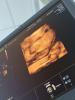

@veronika_30, в 20 недель сын был тоже прям папин и больше инопланетного вида, а это вот 31 неделю вроде) и тут уже прям человек с жирком)

3D УЗИ — это метод медицинского исследования, в ходе которого используются ультразвуковые волны для создания трёхмерных изображений.

Вы очевидно не знаете ,что такое 3Д УЗИ. Это не любая рандомная картинка из интернета. Это картинка конкретного ребенка. Если вы пойдете на 3д в 12 недель ,то конечно там ничего общего после рождения не будет . Зависит от того ,на каком сроке идти на УЗИ . Если пойти ,когда уже человечик сформирован и черты лица сформированы , то это будет внутриутробное фото вашего именно ребенка. А не придуманное фото или видео компьютером .

Это не реальная фотография, а компьютерная модель,созданная на основе данных УЗИ.